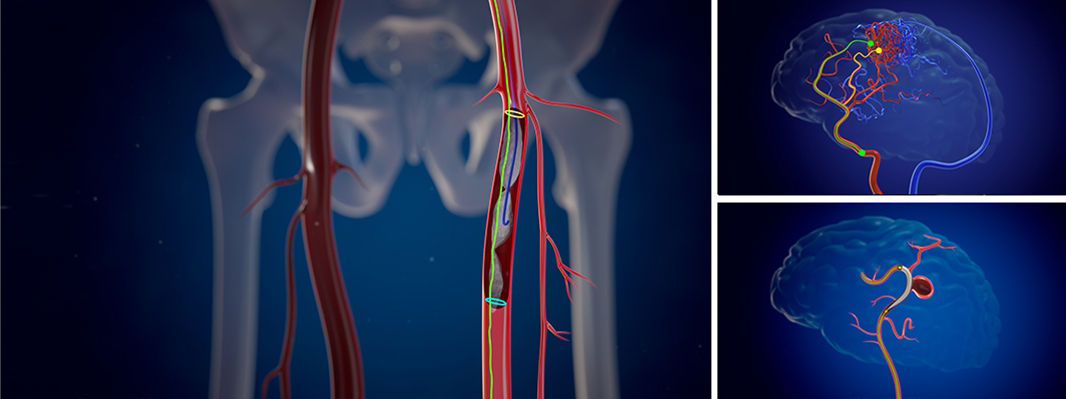

Vessel ASSIST für periphere Verfahren

Bei peripheren, chronischen Komplettverschlüssen (CTO) bietet die Vessel ASSIST-Lösung eine intuitive und genaue Lösung, die Sie bei der Planung und Führung komplexer endovaskulärer CTO-Eingriffe unterstützt. 1

Die automatische Segmentierung von Knochen und Gefäßen und die Mittellinienverfolgung durch den Gefäßverschluss ermöglichen eine schnelle Planung anhand von präoperativen CT- oder MR-Bildern. Durch diese Kombination präoperativer CT- oder MR-Bilder mit Mittellinienverfolgung und Durchleuchtung in Echtzeit können Spezialisten außerordentlich gut sehen, wo die Rekanalisation vorgenommen werden muss und wo sich die Einstichstelle befindet, ohne die Kontrastmittelmenge erhöhen zu müssen.

Vessel ASSIST bietet eine präzise und einfache anatomische Segmentierung und genaue Gefäßquantifizierung anhand von 3D-Volumen. Zudem ermöglichen die erweiterte 3D-Roadmap und erweiterte Bildführungsfunktionen für die frontale und laterale Ebene das sichere Führen von Kathetern.